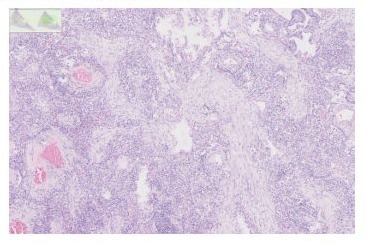

A follow up PET-CT, performed one year after the end of the chest radiotherapy, showed a new hyper metabolic opacity in the posterior lower right lobe highly suspicious for a new neoplastic lesion and in a different location as the one observed earlier (Figure 1). This lesion appeared in an area receiving low dose radiotherapy from the prior course, between 2 and 15 Gy. Its volume and extension towards the mediastinum did not allow a new radiation course. A new brain MR did not reveal any progression or new lesion. A transthoracic biopsy was not performed due to the location of the lesion.

Figure 1: Axial chest HRCT and PET/FDG scan images of localised organising pneumonia manifesting as a single sub pleural mass-like opacity with abnormal 18F ‐fluorodeoxyglucose uptake in the lower third of right lung (lateral and posterior basal segments) associated with satellite infra-centimetric nodular opacities. This radiological aspect is similar to sub pleural metastatic lesion. On the left side, the radiation induced fibrosis.